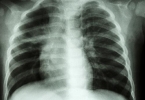

• 胸骨骨折必须卧床平躺吗

胸骨骨折必须卧床平躺吗

胸骨骨折患者是否需要卧床平躺需根据骨折严重程度决定。若骨折无移位且稳定性良好,通常无须严格卧床;若存在明显移位或合并其他损伤,则需短期绝对卧床。胸骨骨折多由外力撞击或挤压导致,如交通事故、高处坠落等。 ...